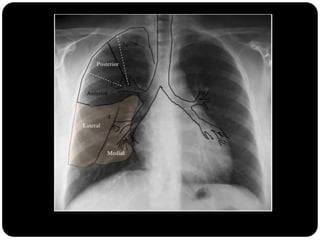

Atelectasia do Lobo Médio

Impacto mínimo

sobre volume total

do hemisfério

direito (é o menor

dos lobos) LS e LI

inferior compensam

a perda de volume;

Atelectasia passiva

Sinal da silhueta

Lobo médio: borra o contorno direito do coração.

Língula: borra o contorno esquerdo do coração.

Segmentos basais: borram o contorno do diafragma*** (olhar

imagens anteriores para ver quais).

1. Qual lobo está afetado? Por quê?

É atelectasia?

Lobo

médio(segmento

medial e lateral;

Borra contorno

cardíaco direito

E não é atelectasia!

A fissura horizontal

não está deslocada.

Qual lobo está afetado? Por quê?

Língula pois borra

contorno cardíaco

esquerdo

Em que lobo está essa lesão?

Resposta: LID

Importância do

perfil;

Importância da

ausência do sinal da

silhueta;